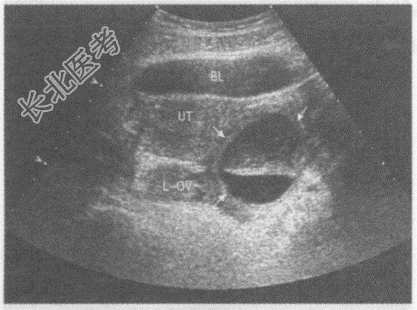

- 单项选择题临床资料:女性, 24岁,常规体检。妇科内诊: 左附件区扪及一肿物,质软。

超声综合描述: 左附件区可见圆形无回声区(箭头所示),边界清晰, 形态规则,上半部透声不清亮, 下半部透声清亮,两层间有一平面, 随体位移动而变化。

其超声提示: A、左卵巢巧克力囊肿

B、左附件区包裹性积液

C、左卵巢宫外孕

D、左卵巢囊性畸胎瘤(脂液分层征)

E、左卵巢囊肿